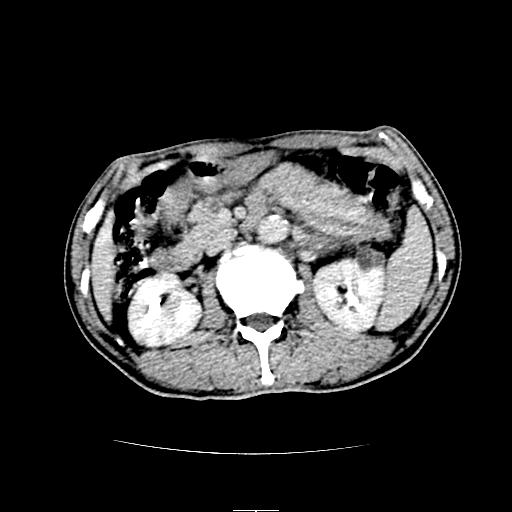

左上腹胃、脾及胰腺间巨大囊性占位性病变,内见多数薄隔,有轻度强化,明显占位效应。左肾见一小囊肿。

考虑:1、左上腹巨大囊肿(可能来源于胰腺)。

2、左肾小囊肿。

左上腹胃、脾及胰腺间巨大囊性占位性病变,内见多数薄隔,有轻度强化,明显占位效应,胰腺及左肾结构清楚,明显向后下方推压 移位。左肾见一小囊肿.多考虑:1 网膜巨大囊肿。2 左肾小囊肿。

考虑胰腺巨大囊肿,左肾低密度灶从形态和强化方式看不象囊肿,应考虑肿瘤。

左上腹胃、脾及胰腺间巨大囊性占位性病变,其内见多数薄隔,有轻度强化,明显占位效应。左肾见一小囊性变。

左肾囊肿;网膜巨大囊肿。